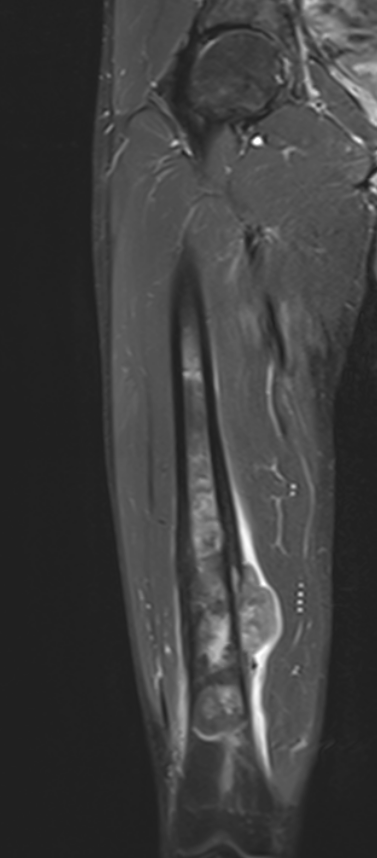

MRI

Evaluate

i) Soft tissue component

ii) Involvement of neurovascular bundle

iii) Marrow extent of tumour

- helpful in determining appropriate resection level

- satellite lesions - metastasis within reactive zone

iv) Identify skip lesions

- metastasis outside reactive zone

- sagittal and coronal images of the entire bone

v) Joint involvement